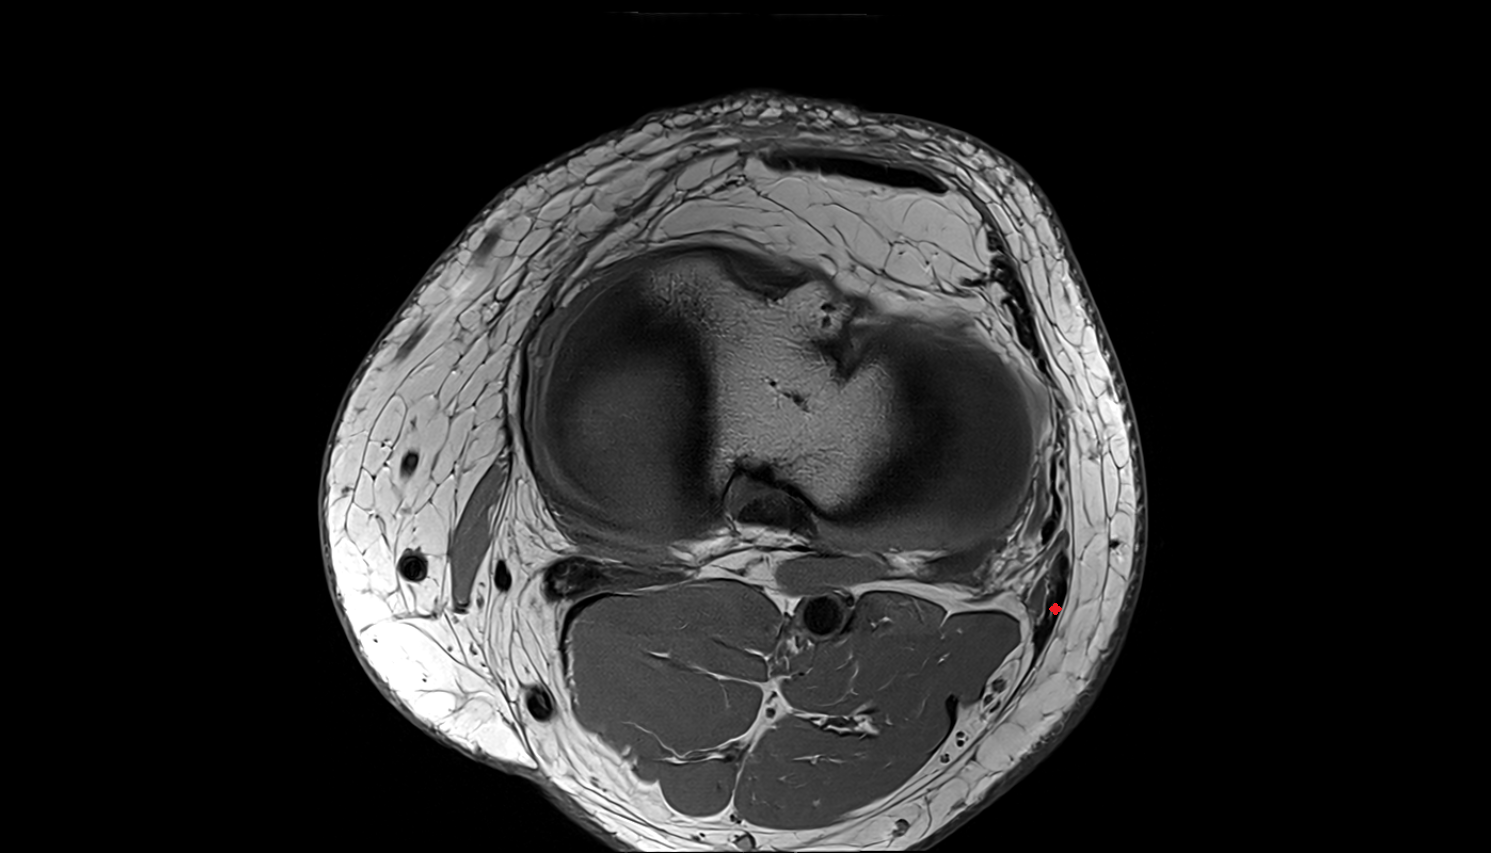

- Knee Joint